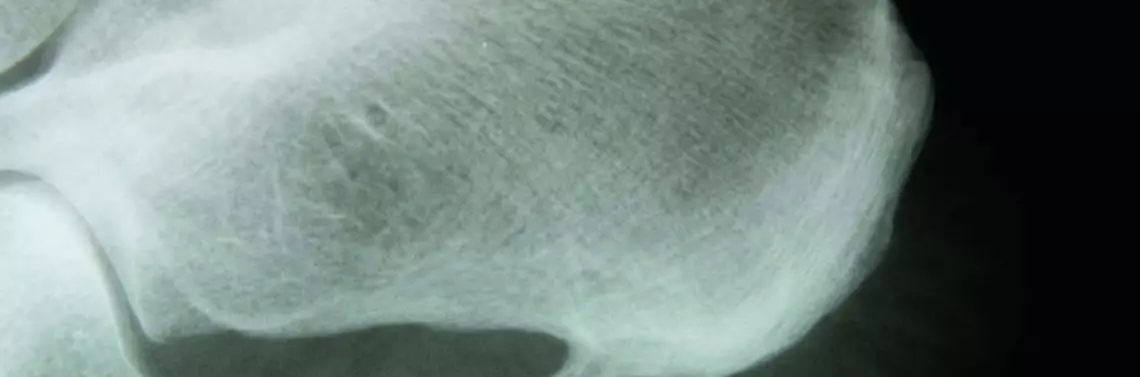

Ostroga piętowa (calacar calcanei) jest to entezofit (czyli narośl kostna) występujący w górnej okolicy wyrostka przyśrodkowego guza piętowego bądź na tylnej powierzchni kości piętowej. Ostroga piętowa podeszwowa wrasta w rozcięgno podeszwowe wzdłuż linii nacisku kości piętowej. Natomiast ostroga piętowa grzbietowa wrasta w ścięgno Achillesa. Rozmiar ostrogi piętowej nie jest zależny od występujących dolegliwości bólowych. Zazwyczaj ostroga piętowa osiąga 2–4 mm. R e k l a m a